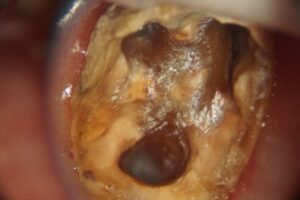

顕微鏡根管治療症例

HOME › 顕微鏡根管治療症例

症例一覧